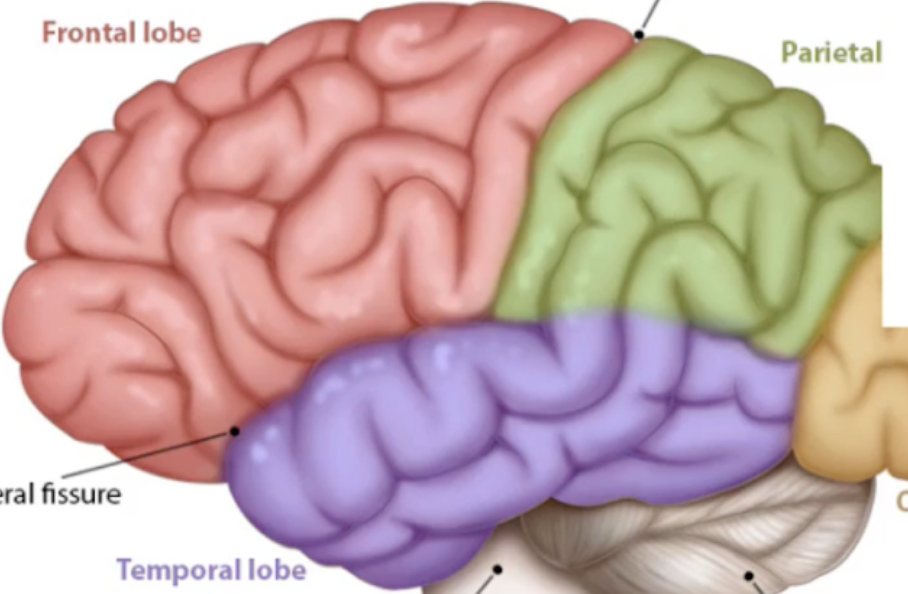

What are the ridges (folds) on the cerebrum called?

Gyrus/Gyri (Peak of the sunchip)

What are the grooves(valley) on the cerebrum called?

Sulcus/Sulci valley between the peak

What separates the two cerebral hemispheres?

Longitudinal fissure

Lobe function: motor speech,memory formation,personality,Emotion

Frontal Lobe

Lobe function: Somatosensory cortex(sense processing), Sensory integration, Spatial awareness

Parietal Lobe

Lobe function: Visual processing and storing visual memories (posterior side)

Occipital Lobe

Lobe functuon haering, language, smell

Temporal lobe